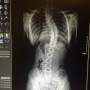

흉추부 X-ray 사진

최근에도 흉추부 관련하여 질문 올렸었는데 , 한달 전 동네 병원에서 X-ray 찍은 모습입니다..

흉추부를 포함하여서 각도를 알고 싶은데 도움 좀 부탁드리겠습니다...

엑스레이 측정 흉추부 45도, 요추부 22도 측정되는 상태입니다.

허리 스트레칭 운동 열심히 하시기 바랍니다.

고려대 구로병원 정형외과 척추측만증 클리닉 서 승 우